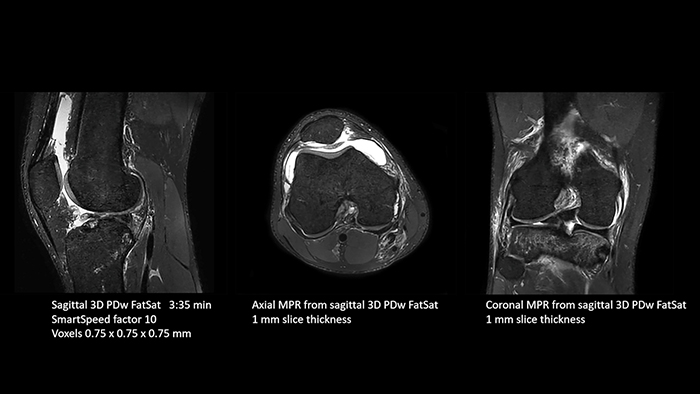

Previously, the practice wasn’t able to use 3D imaging on all joints, because the time required was too long, and on some joints it was simply not possible to achieve a good quality image, Dr. Schröter says. “Now, with SmartSpeed we consistently use 3D imaging for all joints and can thus discover the smallest changes, for example in the cartilage. And that, of course, helps us in making a detailed diagnosis.” Dr. Schröter says their MSK images show high contrast and extremely high quality. He mentions the menisci as an example. “We use a 3D proton density weighted fatsat sequence, thickness is 0.3 mm and scan time 3 minutes. The MPRs show an unbelievable resolution. Very small tears and even fraying of the tip of the meniscus become visible, which is normally only possible in arthroscopic surgery. When imaging the small joints of the fingers and the thumb we achieve extraordinary quality. Using SmartSpeed we succeed in displaying even very small structures anatomically correct, enabling us to see the extent of possible injuries. Tendons and ligaments appear with higher resolution so we can better see the injury pattern and describe and delimit it. Our referring physicians are fascinated by the extraordinary quality and high level of detail of the images. Patients are happy that the examination does not take too long. We hear from patients that it took a lot less time than they expected. This is especially important when scanning patients who are very uncomfortable in the MRI environment.”

SmartSpeed is used to reduce scan times. All three PDw orientations were obtained with only one 3D sequence using SmartSpeed. Performed with 1.5T Ambition X, 16ch dS Knee coil.